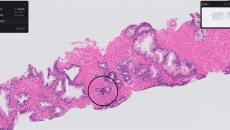

Paige Prostate analyzes digitized biopsy slides and identifies areas that could be cancerous for the pathologist to review further.